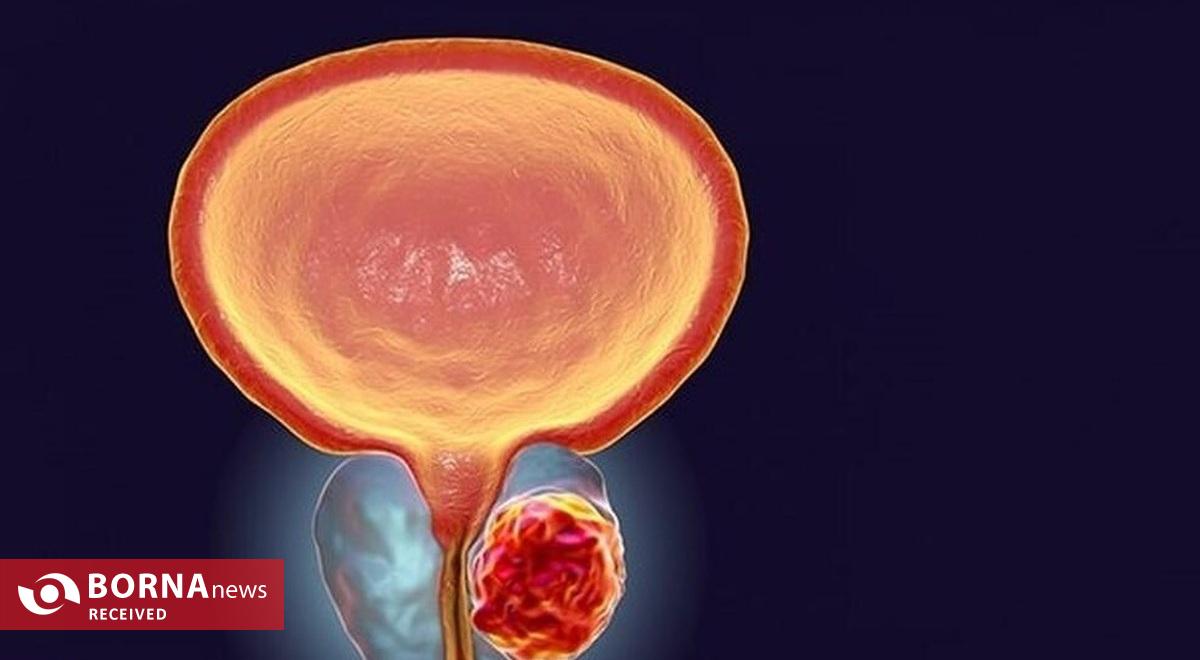

مدل نرمافزار تلفن همراه با قابلیت تشخیص سرطان پروستات توسط هوشمصنوعی تهیه شد.